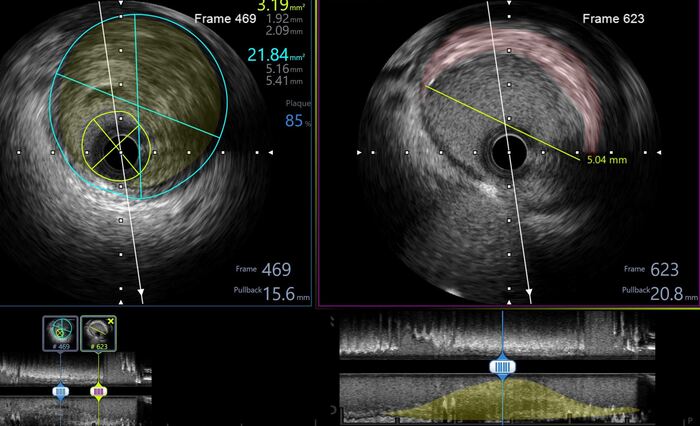

Делает ВСУЗИ (внутрисосудистое ультразвуковое исследование = специальный датчик заводится в сосуд через катетер и он изнутри датчик сканирует сосуд ультразвуком, в нашем случае частотой 40 Мгц)

Картина на ВСУЗИ:

Выявлена в начальном сегменте ПМЖА большая нестабильная атерома (желтым) с липидным ядром с распадом, на устье ПМЖА уже сформирована фиброзная атеросклеротическая бляшка (красным) с переходом на ствол левой коронарной артерии. Сама артерия по ВСУЗИ большая